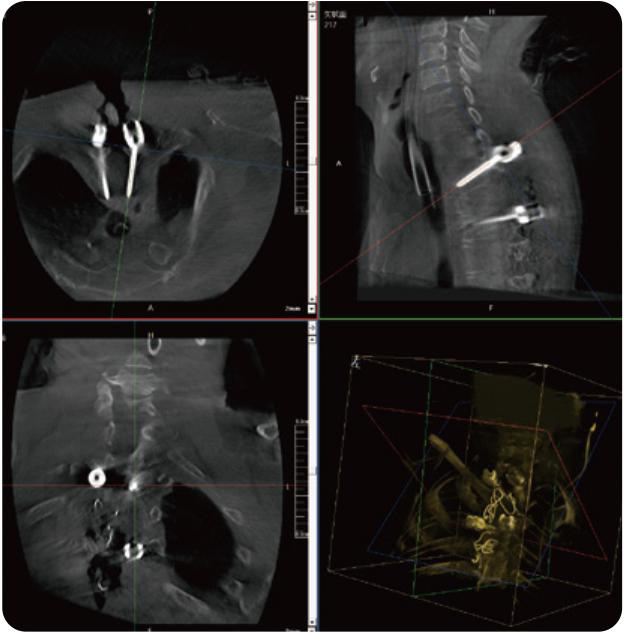

PL300B可應用于多節段脊柱外科手術(shù),輔助醫生定位病灶部位,為脊柱外科手術(shù)(經(jīng)皮椎體成形術(shù)、椎弓根螺釘內固定術(shù)等術(shù)式)提供術(shù)前手術(shù)流程規劃、入釘位置、角度可視化引導,模擬仿真入釘輔助。

PL300B搭配普愛(ài)醫療自主研發(fā)生產(chǎn)的平板3D C形臂,借助一體化自適應配準( 軌跡配準)技術(shù),通過(guò)追蹤C形臂三維采集軌跡,自動(dòng)完成圖像坐標建立和系統坐標配準。配準精度更高,操作步驟少,系統運作效率高。